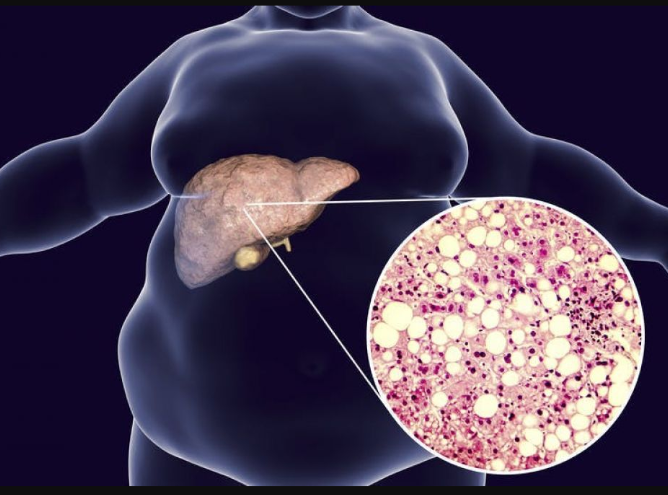

Es un problema que aqueja a millones de personas, aunque muchas de ellas aún no lo saben. Por lo general se produce cuando el hígado comienza a almacenar grasas de manera excesiva en sus célulasEl hígado graso produce inflamación y, si no se trata a tiempo, puede avanzar hasta convertirse en cirrosis.